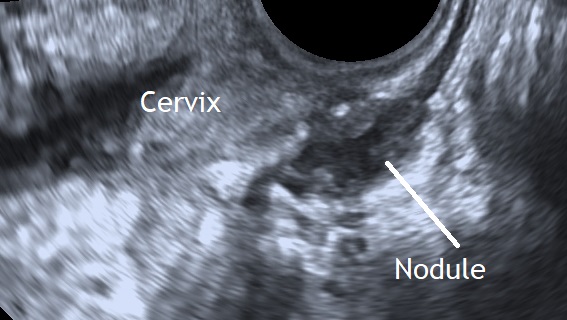

Posterior compartment deep infiltrating endometriotic lesions appear as a hypoechoic thickening of the wall of the bowel or vagina, or as hypoechoic solid nodules which may vary in size and have smooth or irregular contours (Guerreiro et al., 2016).